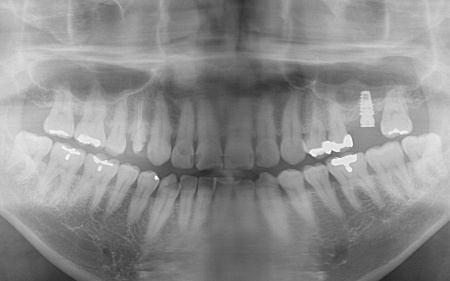

40代男性 長年放置していた虫歯や根尖性歯周炎などの口腔トラブルを全体的に治療した症例

「虫歯を長年放置してしまったので治療をしたい。また、見た目や噛み合わせの改善などを含めた、全体的な治療も行いたい」とご相談いただきました。

患者様は、10年ぶりに歯科医院を受診したとのことです。

レントゲン撮影をして詳しく検査したところ、複数の小さな虫歯が見られました。

また右上奥歯には、歯根の先に炎症が起きて膿が溜まる根尖性(こんせんせい)歯周炎が認められます。

さらに、左上奥歯(第1大臼歯)は温存が難しい状態でした。

③温存が難しい左上奥歯(第1大臼歯)は抜き、骨を再生させる処置「GBR(骨造成)」を行ったのち、人工歯根を埋め込む「インプラント治療」により噛む機能を回復させます。

左上奥歯1本は抜き、GBRで骨を再生させたのち、インプラントを埋入します。

インプラントに装着する人工歯の素材には、自費診療の白いセラミックを選択しました。